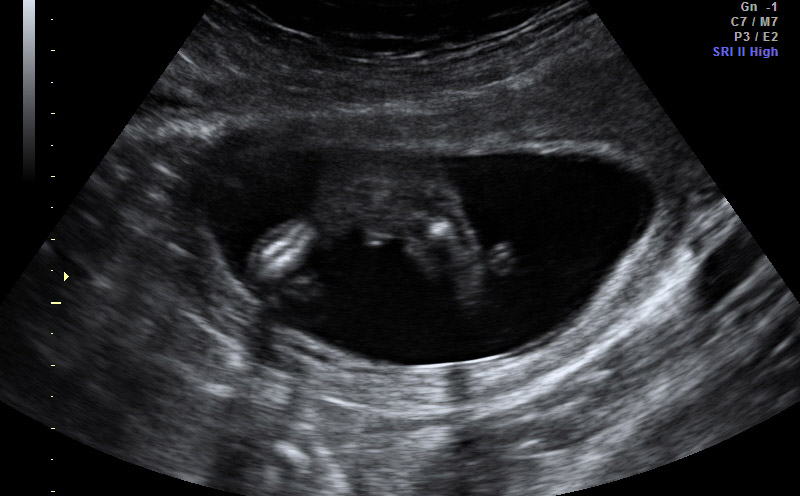

Had an elective u/s today @ 15 wks. Tech said girl, looking for some confirmation. The third pic has me a little confused, but she said that wasn't a good shot. Looking for you wonderful ladies to weigh in! TIA!! Attachment 23883Attachment 23884Attachment 23885